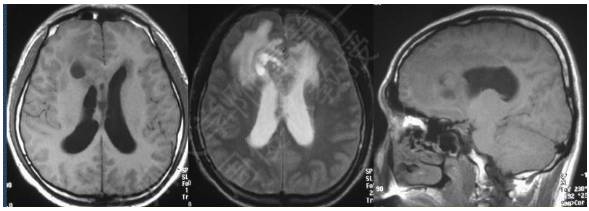

病例:男性,30岁,头痛2月

MR平扫

病理结果:富于淋巴浆细胞型脑膜瘤,WHO I级

2、CT密度较高,钙化少见。MR T1信号等或稍低、T2信号稍低或稍高,增强后呈明显强化;病灶内或边缘可见T1低信号、T2高信号区,增强后不强化;病灶边缘可见广泛增厚的脑膜强化。肿瘤界限模糊,似炎症,累及皮层,瘤周水肿明显(特征性表现)。

3、此亚型脑膜瘤有丰富的慢性炎细胞浸润,易伴发造血组织异常。病理上以上皮细胞增生伴大量淋巴细胞、浆细胞浸润为特点。